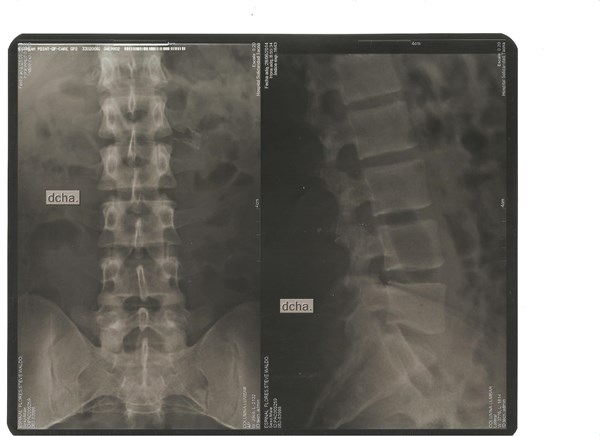

Radiografía lumbosacro por posible hernia

Todo empezó hace varios meses un día desperté con adormecimiento de los dedos del pie con hormigueos me pare y no podía pisar bien me dolía la ingle por 1 semana estuve ah si después poco a poco después de varios días disminuyo el dolor y el adormecimiento pero note después al tocarme una vertebra con el dedo por la zona lumbar me dolía mucho ese dolor también ya no es ta fuerte ahora ya pasaros 2 meses y las molestias han disminuido pero cuando cargo una bolsa o una mochila con algo de peso empieza las molestias al caminar y camino mal y también aveces me duele el coxis izquierdo y el derecho ya han pasados varios mese y hoy fui al traumatólogo porque quiero regresar al gym y el traumatólogo me dijo que me tome una radiografía lumbosacro fui de nuevo donde y descarto una posible hernia pero me dijo que en la radiografía lumbosacro mi columna esta un poco recta ... Que es lo que creen que haya tenido antes y que es lo que tengo ahora y cuanto tiempo tengo que esperar para regresar al gym.